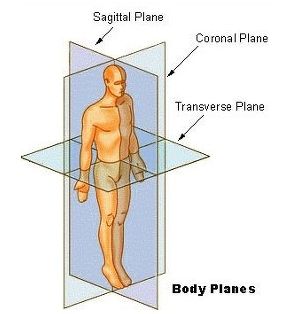

矢状面、冠状面、水平面が分からない? これで完全理解!! 身体の方向をあらわす3つの基準面 矢状面、冠状面、水平面 、本当に理解している?ここって、結構間違えやすい部分だよね。 なので、今回は「矢状面 正中面 」「冠状面」「水平面」のそれぞれの覚え方を。

身体の方向をあらわす3つの基準面 矢状面 正中面 、冠状面、水平面 のイラスト🎨 フリー素材 看護roo! カンゴルー。

矢状面、冠状面、水平面が分からない? これで完全理解!! 身体の方向をあらわす3つの基準面 矢状面、冠状面、水平面 、本当に理解している?ここって、結構間違えやすい部分だよね。 なので、今回は「矢状面 正中面 」「冠状面」「水平面」のそれぞれの覚え方を。

身体の方向をあらわす3つの基準面 矢状面 正中面 、冠状面、水平面 のイラスト🎨 フリー素材 看護roo! カンゴルー。

人体の基準面で矢状面 と 冠状面 がごっちゃになる人へ。 このイラストのイメージがあると記憶に残ります。

矢状面、冠状面、水平面が分からない? これで完全理解!! 身体の方向をあらわす3つの基準面 矢状面、冠状面、水平面 、本当に理解している?ここって、結構間違えやすい部分だよね。 なので、今回は「矢状面 正中面 」「冠状面」「水平面」のそれぞれの覚え方を。

矢状面、冠状面、水平面が分からない? これで完全理解!! 身体の方向をあらわす3つの基準面 矢状面、冠状面、水平面 、本当に理解している?ここって、結構間違えやすい部分だよね。 なので、今回は「矢状面 正中面 」「冠状面」「水平面」のそれぞれの覚え方を。